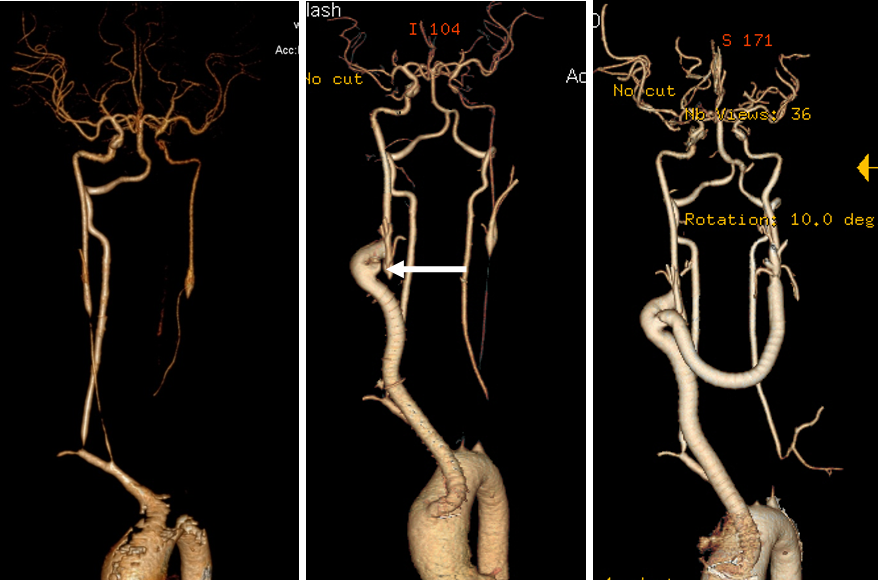

★ 病例1(女性,30岁)

症状:头晕、复视、左手麻木;ESR 5mm/h, CRP 2.1mg/dl。

诊断:双侧颈总动脉及左锁骨下动脉闭塞。

启示:颈内/椎动脉可有效代偿;避免同期重建多支血管以防高灌注风险。

头晕及视力减弱进行性加重